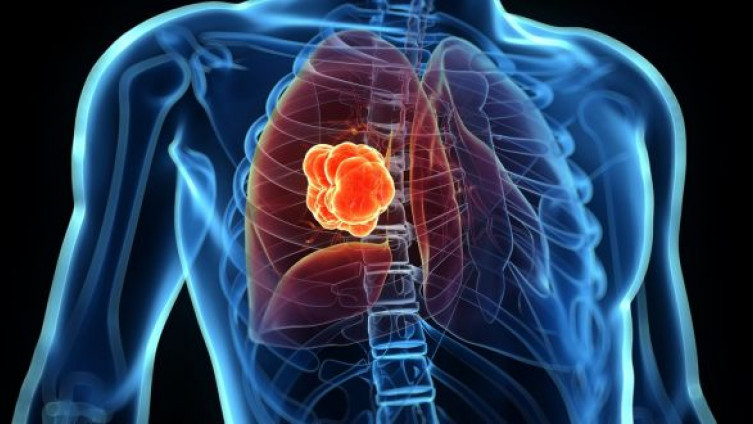

Karcinom pluća na godišnjem nivou odnese više od 1.6 miliona života, što je više od karcinoma dojke, prostate i kolona zajedno. Kasno javljanje simptoma kao i nedostatak adekvatnih metoda rane detekcije bolesti predstavljaju kamen spoticanja zdravstvenih radnika već više od pola stoljeća.

Ukoliko je već došlo do oboljenja, brzo postavljanje dijagnoze i rano započinjanje tretmana može u znatnoj mjeri poboljšati izglede pacijenta za preživljavanje.

Zbog podmukle prirode karcinoma pluća, na žalost, kod velikog dijela, gotovo većinee većine pacijenata dijagnoza se postavlja prekasno tj. kada se bolest već proširila organizmom.